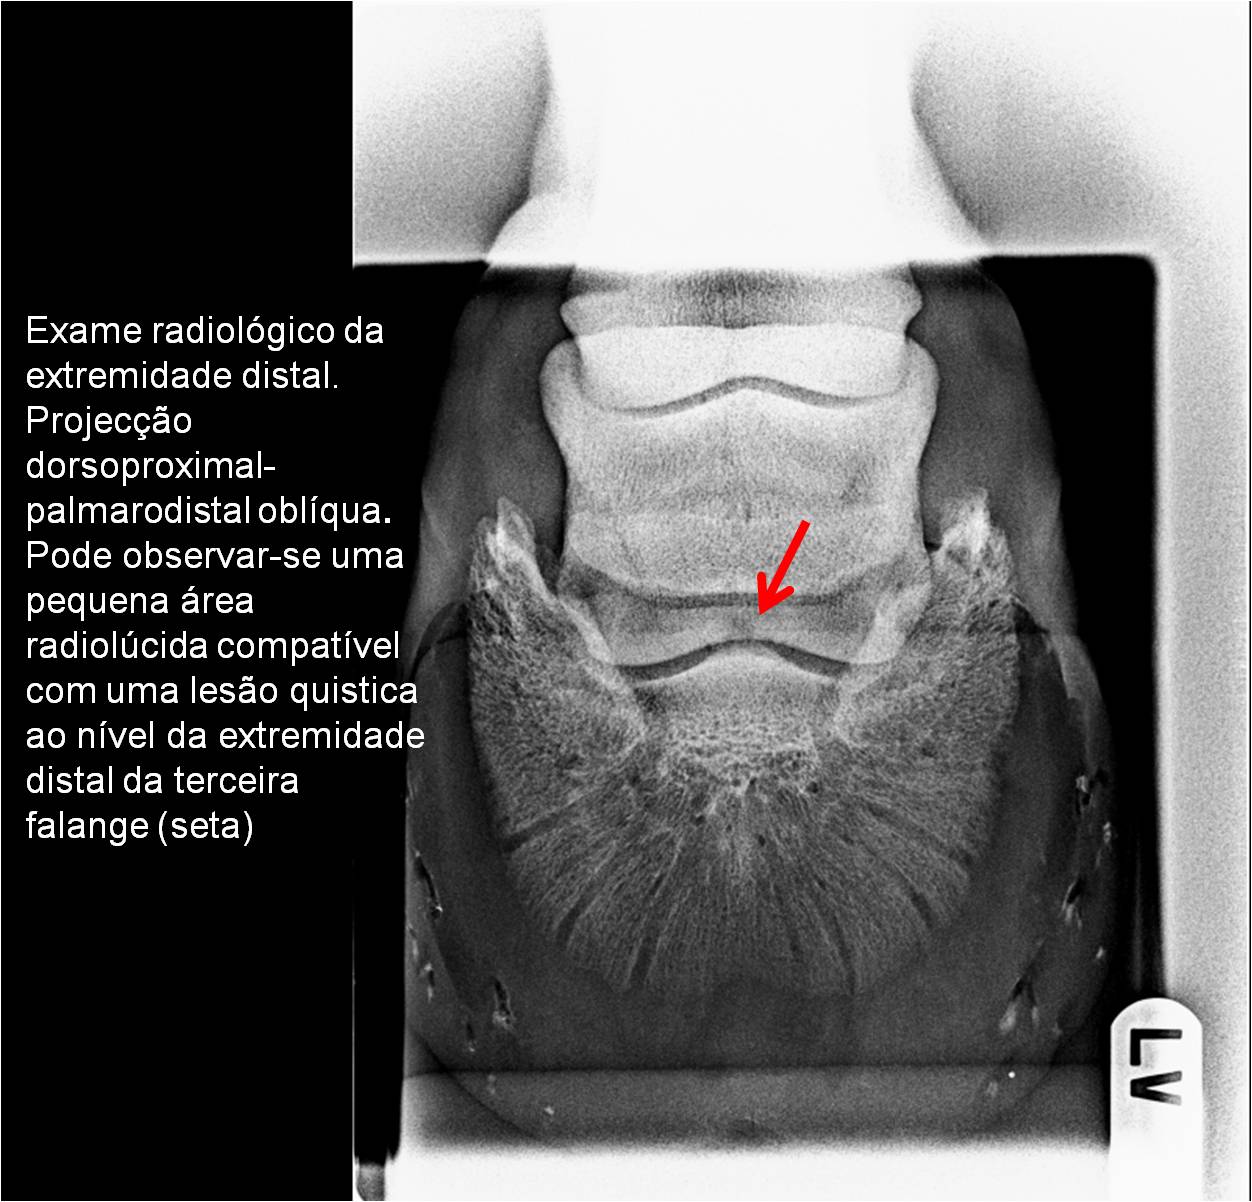

Publisher: Universidade de Évora

Abstract: O relatório de estágio encontra-se estruturado em três partes distintas. A primeira parte faz a caracterização das infraestruturas e funcionamento do Hospital Veterinário de Equinos de Lüsche, Oldenburg, Alemanha, assim como a análise casuística dos casos clínicos acompanhados durante os 6 meses de estágio. A segunda parte consiste de uma revisão bibliográfica sobre quistos do osso subcondral em equinos. Por fim, a terceira parte consta da apresentação e discussão de um caso clínico, nomeadamente o diagnóstico e acompanhamento imagiológico, por ressonância magnética, de um quisto subcondral na terceira falange num cavalo adulto; ### Abstract Equine Practice- Subcondral bone cyst of the third phalanx This internship report is divided in three parts. The first part characterizes the infrastructure and function of the Equine Hospital Lüsche, Oldenburg, Germany, as well as the casuistic of the clinical cases accompanied during the 6 month internship. The second part consists in a bibliographic review of cystic lesions of the subchondral bone in equines. The third part consists in a case report, the diagnostic and imagiological accompaniment, by use of magnetic resonance imaging, of a subchondral bone cyst in the distal phalanx of an adult equine.